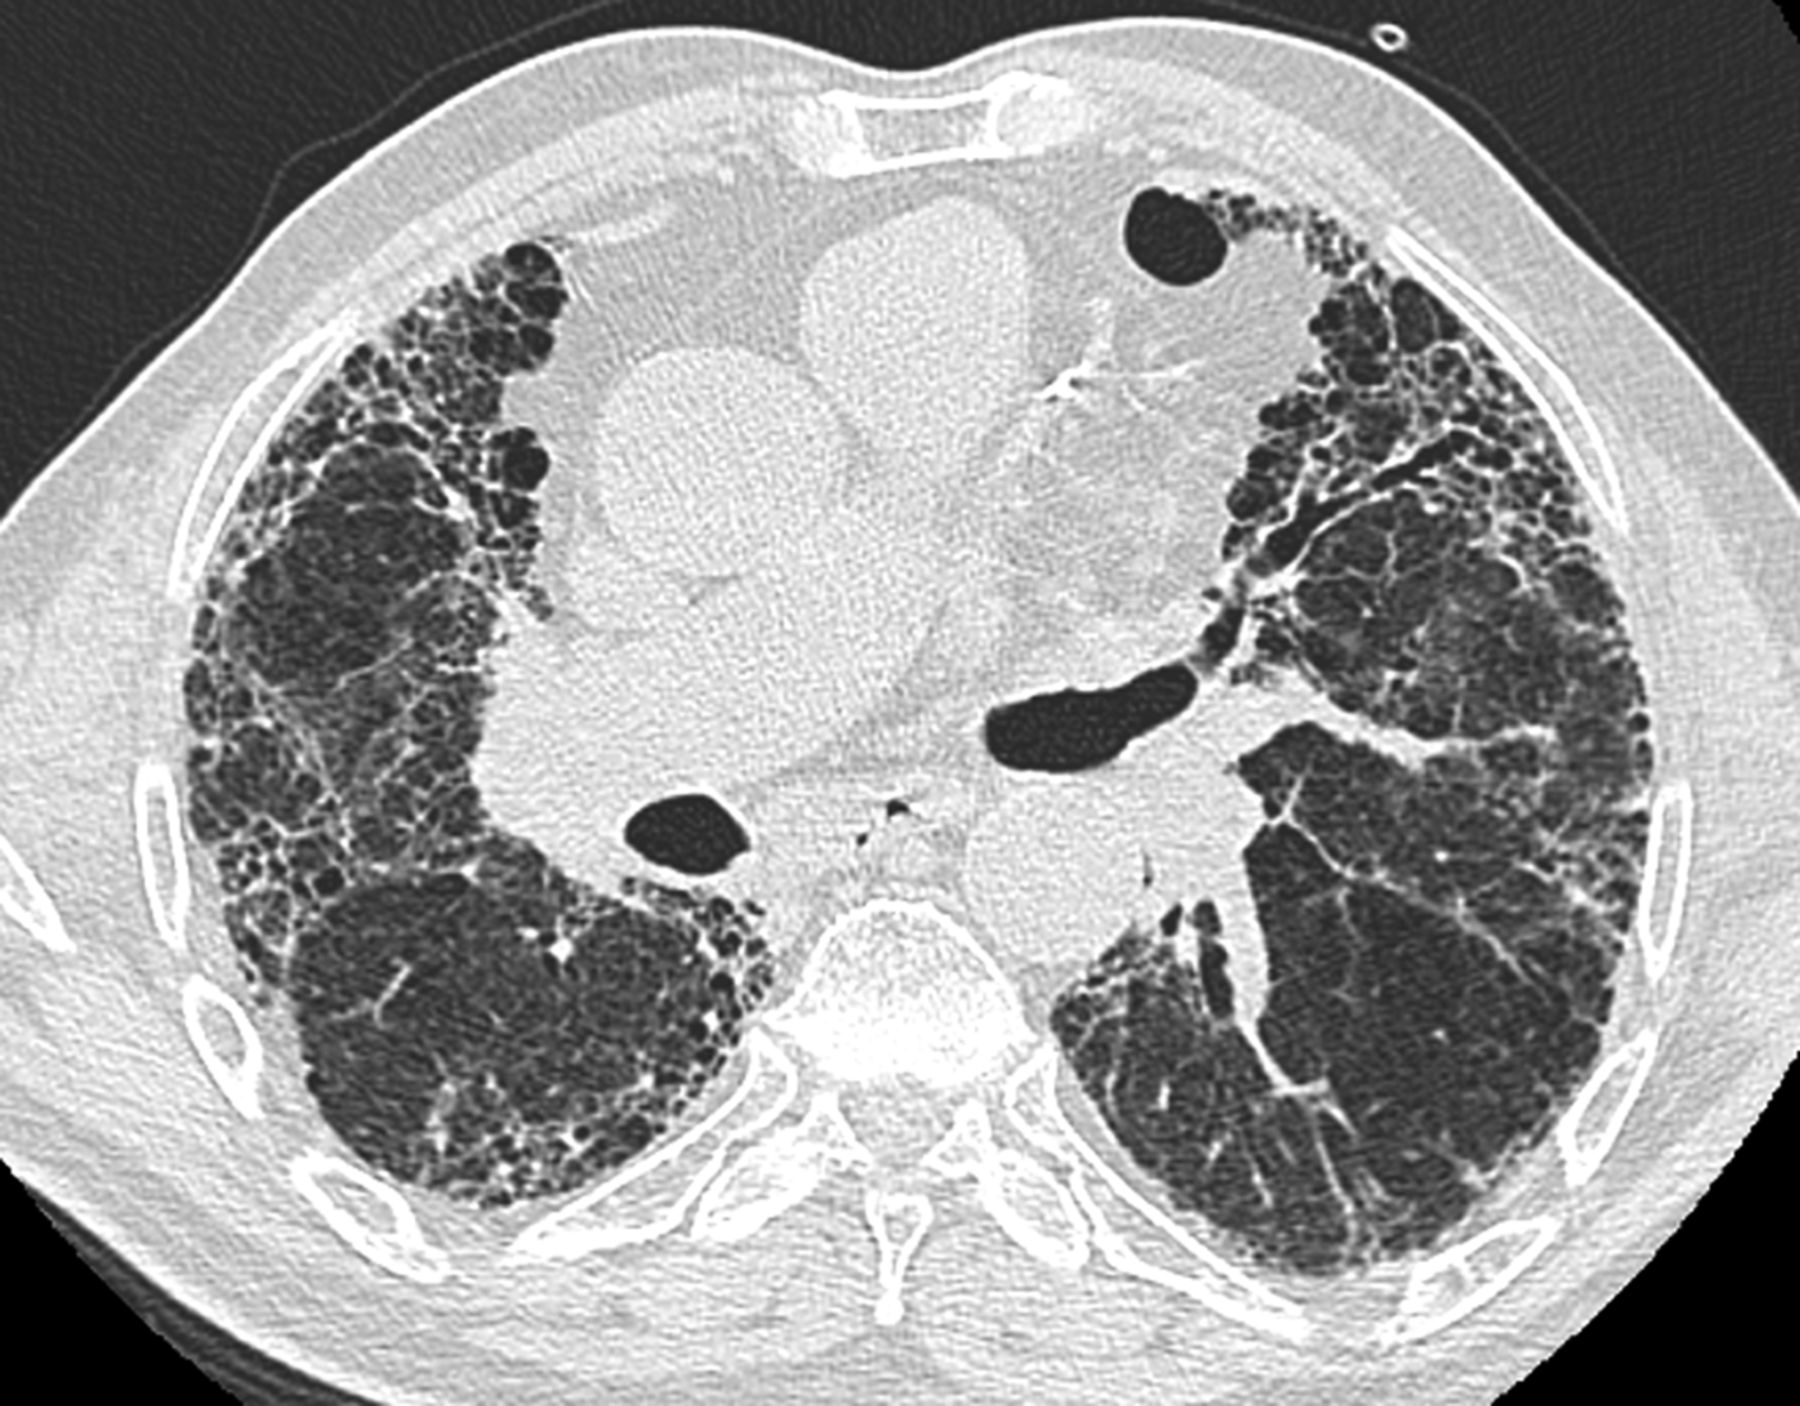

_右肺纖維化CT檢查

_特發性肺纖維化的高清CT圖像

_特發性肺纖維化ct表現圖